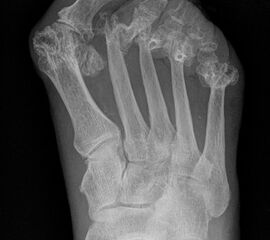

Deutlich bessere Ergebnisse wurden erreicht durch eine Kombination der OP nach Tillmann mit einer Arthrodese des Großzehengrundgelenks oder auch einer Lapidus-Arthrodese 611. Dies wurde bereits 1956 durch Vainio empfohlen, hat sich aber erst in diesem Jahrtausend flächendeckend durchgesetzt 121314.

Die Operation nach Hoffmann-Tillmann (Abb. 4) ermöglicht durch die Resektion der Metatarsaleköpfe die Reposition der Zehen, da hierdurch der notwendige Platz geschaffen wird (Tillmann 1990). Meist sind nicht nur die knöchernen Strukturen der Metatarsaleköpfe destruiert, auch das plantare Polster ist disloziert, regelmäßig kommt es zur Ruptur der plantaren Platten mit Destruktion der Kapsel-, Band- und Sehnenstrukturen (Tillmann 2009) 6. Häufig findet man ausgeprägte Rheumaknoten oder Bursitiden plantar. Durch die breite, querovaläre Hautexzisionaus dem Vorfußballen werden plantare Schwielen entfernt, später beim Hautverschluß werden die plantaren Strukturen durch die plastische Dermatodese wieder in die Belastungszone reponiert.

Es sollten immer alle MT Köpfe II-V reseziert werden, um einen harmonischen Metatarsale Index mit genauer Längenabstimmung herzustellen und keine Druckspitzen durch überlange Metatarsalia zu provozieren. Die kann in Einzelfällen bedeuten, dass ein weniger destruiertes Gelenk zwischen oder am Rand der metatarsalen Reihe geopfert werden muss. Die Operation nach Hoffmann-Tillmann wird meist ab LDE Stadium IV und V indiziert (Tabelle 1).